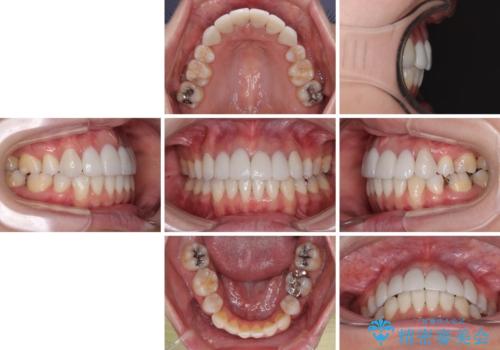

歯並びだけでなく、歯の色も明るくなり、すっきりとした口元の印象となりました。

- 前歯の八重歯やデコボコを気にして来院された患者様です。

口元の突出感はありませんが、前歯の重なりが著しいため、目立ちにくい表側のワイヤー装置にて、上下左右の第一小臼歯4本を抜歯して矯正治療を行うこととしました。

上顎前歯4本は、以前むし歯により神経をすべて取り除かれており、その影響で既に変色を起こしている状態でした。

4本とも歯根部先端の骨が炎症により吸収していることがレントゲン写真から示唆されたため、矯正治療後に4本を再根管治療し、その後上顎6歯をオールセラミッククラウンにて補綴治療することとしました。